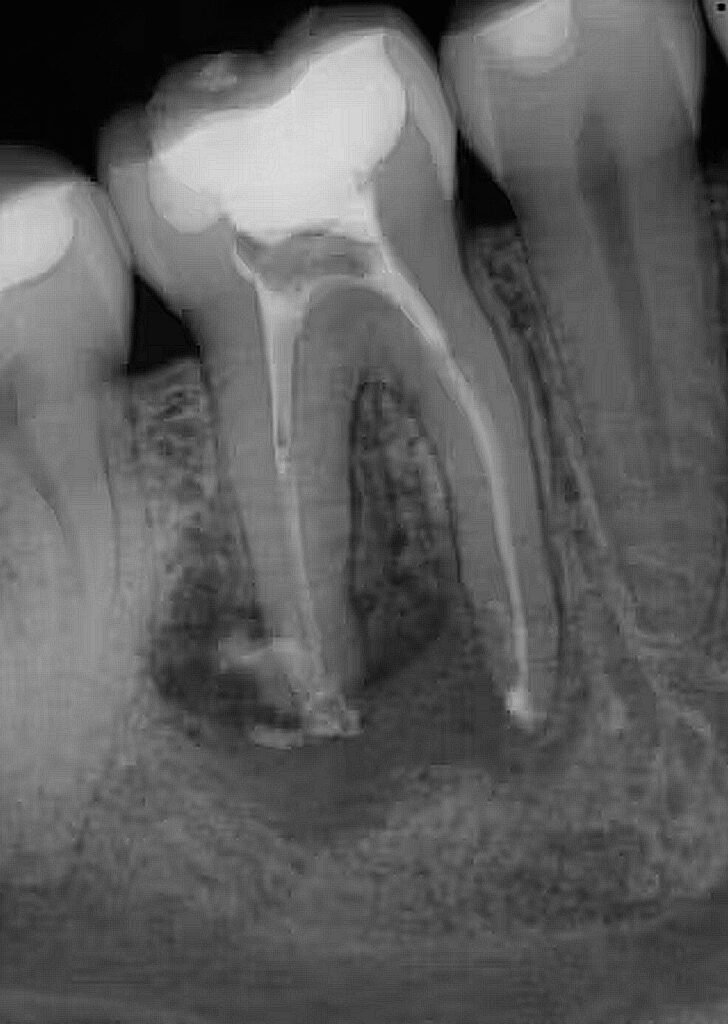

Standard 2D X-rays can hide curved roots or extra canals. At Finesse Dentistry, we use 3D CBCT Scans to see your tooth from every angle before we even touch an instrument. This technology allows us to:

- Evaluate every tooth in 360 degrees to see what can be saved versus what is truly beyond repair.

- Plan the exact path of removal and protect essential anatomy like nerves and sinuses.

- Section molar roots into smaller parts for a quicker, less traumatic “divide and conquer” exit.